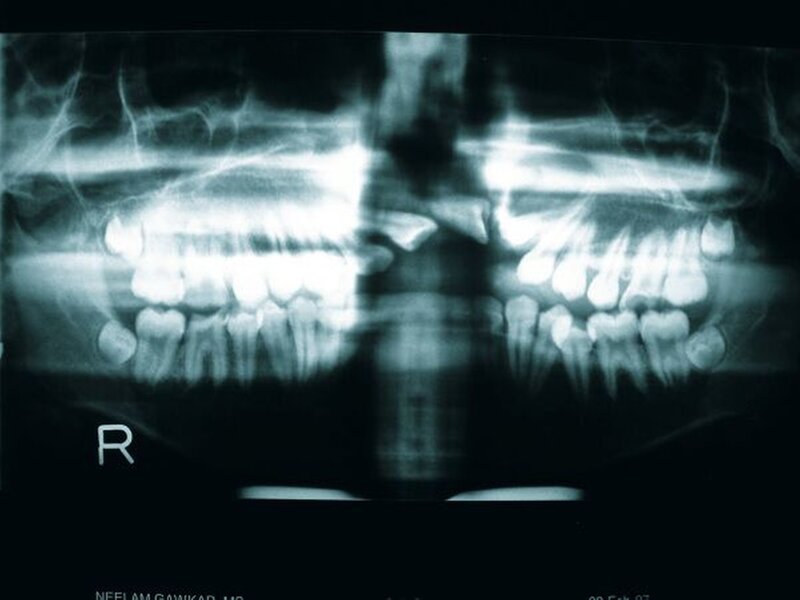

Das linke Nasenloch war um die Spalte herum erweitert, die Nase selbst durch eine Verschiebung in die kontralaterale Gesichtshälfte deformiert. Es bestand eine Protrusion der Zähne 12, 11 und 13 nach vestibulär durch die Spalte. Enoral imponierte weiterhin eine offene Gaumenspalte (Abbildung 2). Die Molaren befanden sich in Klasse-I-Okklusion nach Angle, ein interdentales Spacing konnte zwischen den Zähnen 13 bis 24 befundet werden; 11 und 21 waren rotiert, 22 nicht zu sehen. Im anterioren Bereich des rechten Oberkiefers hatte sich ein skelettal offener Biss entwickelt. Während des Sprechens oder Schluckens kam es zu einem Vorstrecken der Zunge.

Die radiologische Untersuchung bestand aus einem Orthopantomogramm (OPTG), einer Aufbissaufnahme sowie einer Fernröntgenseitaufnahme (FRS). Neben der Übersicht der Gebissituation mit Nachweis des nicht durchgebrochenen Zahnes 22 im OPTG (Abbildung 3) war in der Aufbissaufnahme der Umfang der knöchernen Gaumenspalte klar zu erkennen (Abbildung 4). Das FRS ließ – bis auf die vertikal anterior verkürzte Maxilla und eine Protrusion der anterioren Prämaxilla – einen weitgehend normalen knöchernen Befund diagnostizieren (Abbildung 5).